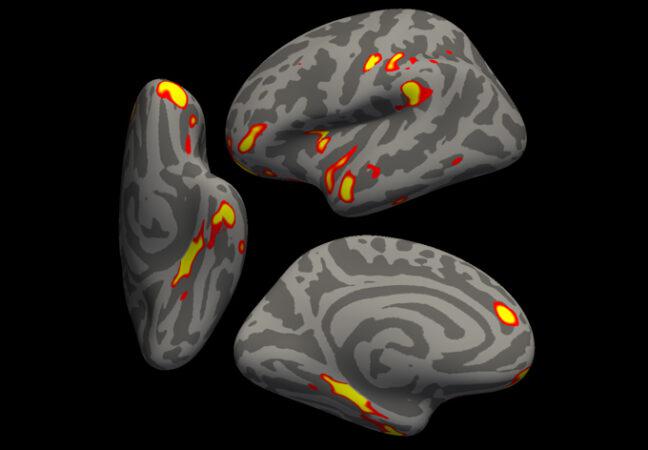

Sau khi bị mắc COVID-19, trung bình người bệnh có ít chất xám hơn trong các bộ phận của não giúp xử lý khứu giác.

Một số vùng não liên quan đến khứu giác bị nhỏ hơn (vùng đỏ và vàng) sau khi bị nhiễm SARS-CoV-2

Vậy nhiễm SARS-CoV-2 có hại cho não không, và nếu có, thì tệ như thế nào? Hiện nay, các nhà khoa học chưa thể trả lời chính xác các câu hỏi này. Nhà khoa học Gwenaëlle Douaud, thuộc Khoa Khoa học Thần kinh Lâm sàng Nuffield tại Đại học Oxford (Anh), cho biết: "Chúng tôi khá ngạc nhiên khi thấy sự khác biệt rõ ràng trong não, ngay cả khi bị nhiễm trùng COVID-19 ở thể nhẹ. Điều đáng lo ngại là những thiệt hại này sẽ kéo dài và khiến những người nhiễm bệnh dễ mắc các bệnh về não hơn trong tương lai".